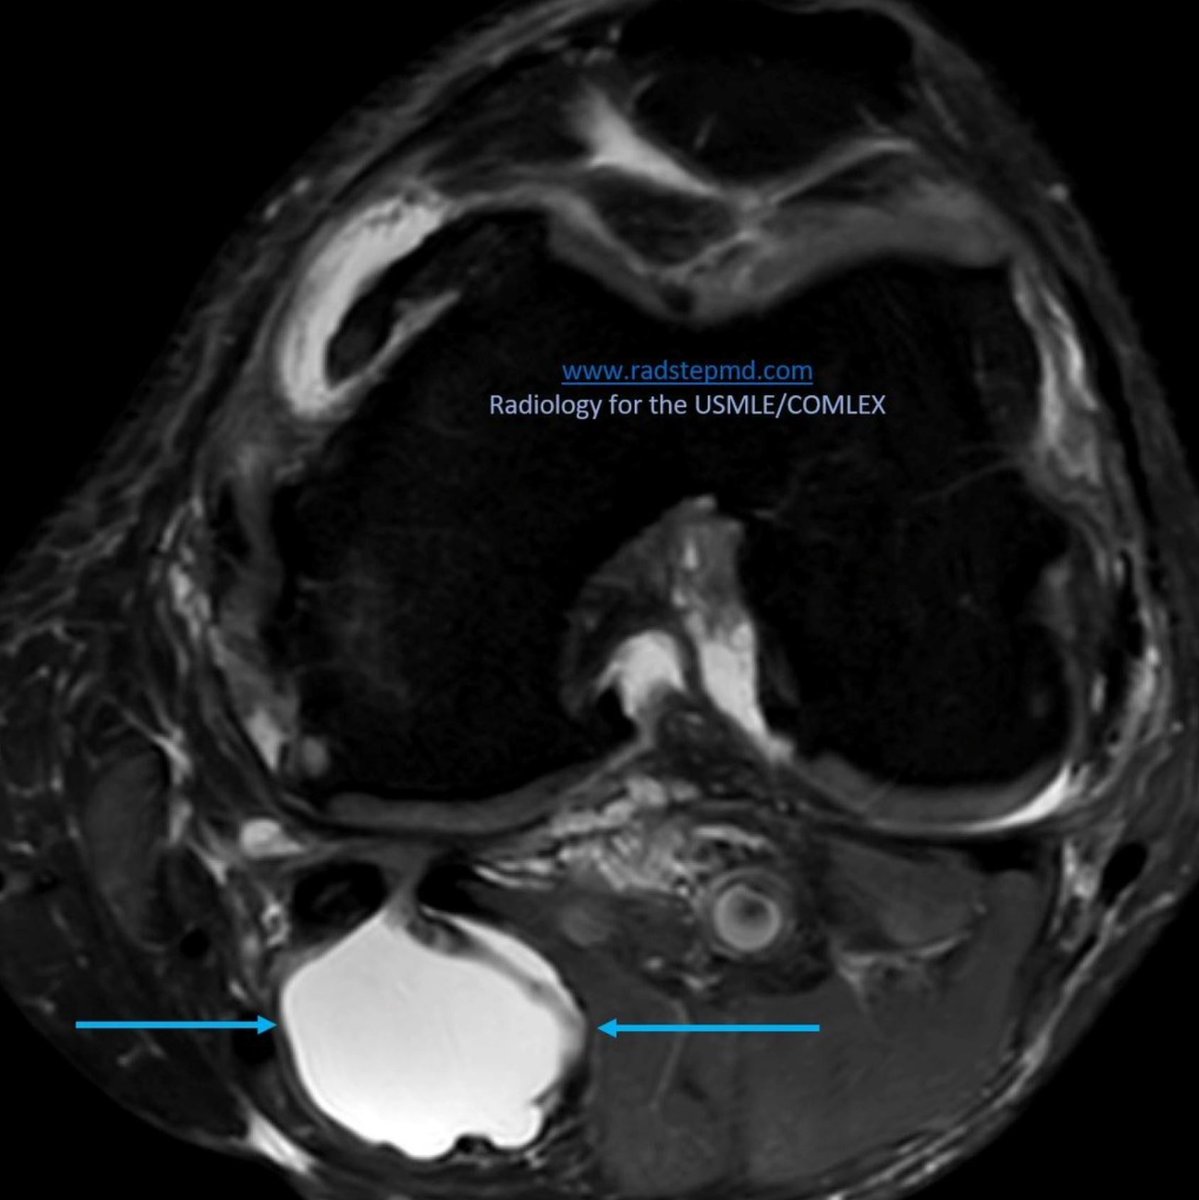

Todays images look at BAKER’S CYST radstepmd.com IMAGING: Collection of synovial fluid in the gastrocnemius-semimembranosus bursa USMLE POINTS: Posterior knee stiffness May form in the setting of chronic degenerative or inflammatory joint disease

IMAGING:

Collection of synovial fluid in the gastrocnemius-semimembranosus bursa

USMLE POINTS:

Posterior knee stiffness

May form in the setting of chronic degenerative or inflammatory joint disease